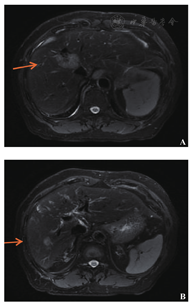

2012年7月起接受6次XELOX方案化疗,此后卡培他滨单药化疗1年;2013年7月影像学检查提示转移灶较前进展,肝脏出现新发转移灶;2013年9月16日针对肝转移瘤行射频消融术,2013年11月复查见肝Ⅷ段近膈顶处出现新病灶(图2)。2014年6月肺部CT未见明确转移灶,2014年11月右下肺考虑转移灶(图3)。2015年3月肺转移瘤较前进展,2015年3月起接受6个疗程FOLFIRI方案化疗(伊立替康150 mg/m2,ivgtt+氟尿嘧啶340 mg/m2,iv bolus+氟尿嘧啶2.2 g/m2,civ+亚叶酸钙330 mg/m2,ivgtt),2015年9月肝肺转移瘤均较前进展,2016年1月21日行肝转移瘤切除术,2016年2月胸部CT提示肺转移瘤进展,患者拒绝肺转移瘤介入治疗,2016年3月和4月行树突状细胞治疗。2017年3月肺CT:肺转移瘤增大,肝脏MRI肝Ⅷ段肿瘤存活(图4A),Ⅵ段新发转移癌(图4B)。2017年3月22日继续行FOLFIRI方案化疗,2017年4月—10月行10次西妥昔单抗+FOLFIRI方案化疗(伊立替康162 mg/m2,ivgtt+氟尿嘧啶365 mg/m2,iv bolus+氟尿嘧啶1.7 g/m2,civ+亚叶酸钙365 mg/m2,ivgtt+西妥昔单抗700 mg,ivgtt),2017年11月—2018年1月行5次西妥昔单抗单药(700 mg, ivgtt)靶向治疗,随访至2018年1月28日,生存时间超过94个月。